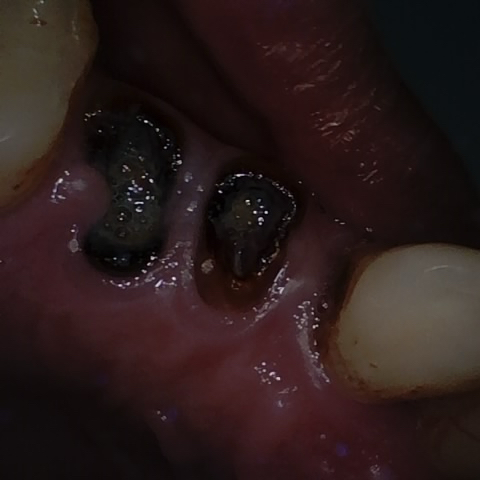

Annotated as "Good"